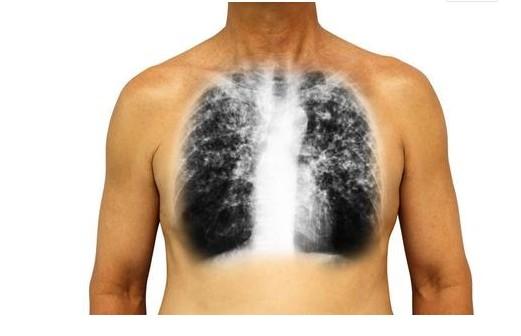

肺癌是惡性腫瘤之一,居男性惡性腫瘤首位,每年新發超過60萬人,平均每隔30秒就有一人病於肺癌。

一提到肺癌,多數人就會想到咳血、消瘦,其實,肺癌還有其他不典型的症狀。

一旦「這裡」開始疼,十有八九是肺癌,三類人最好去檢查一下!